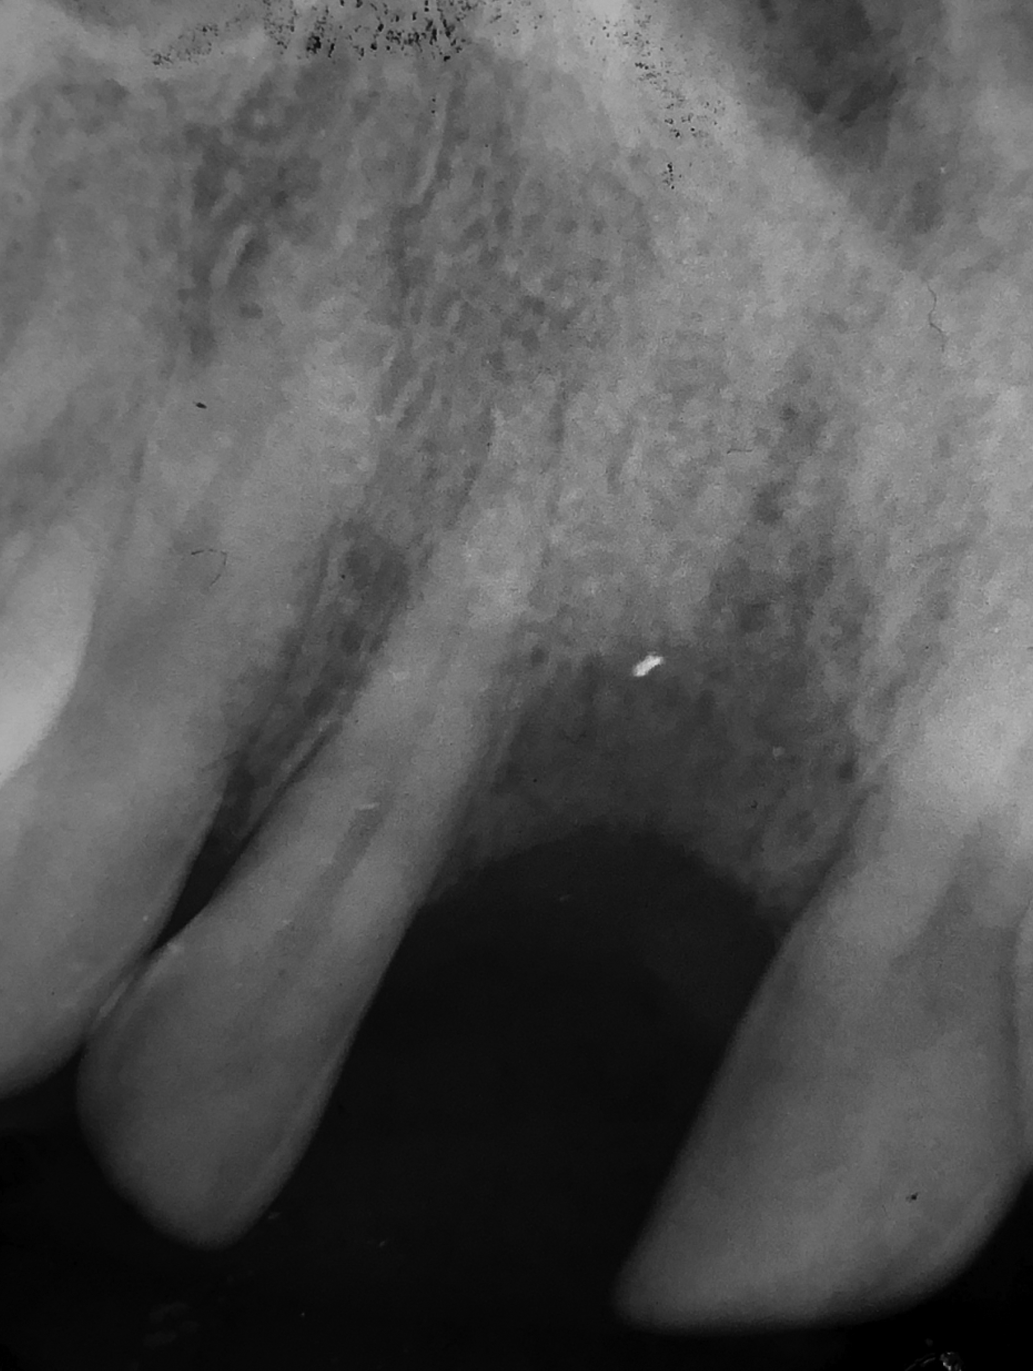

Ein Implantat mit Ø 3,7 mm und der Länge von 12 mm wurde im November 2001 eingesetzt. Das Kontrollbild wurde 5 Monate nach der Implantation gemacht.